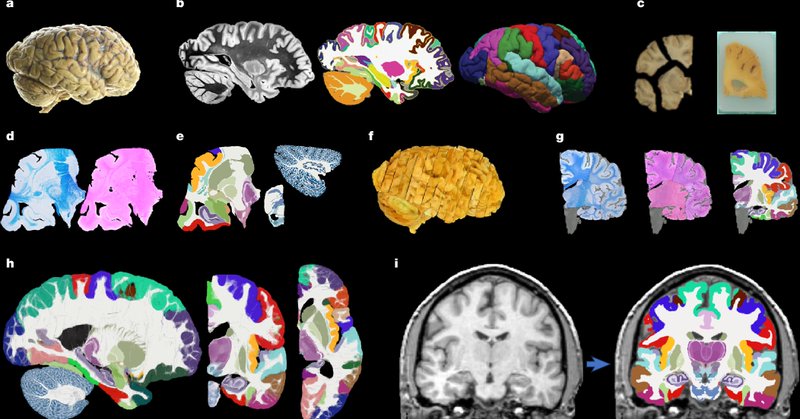

Ten years (!) after submitting the grant, NextBrain is published in @Nature . NextBrain is a brain atlas built from 3D histology that enables segmentation of 3D brain scans (MRI, Hip-CT, even photos!) into hundreds of regions. Article, data, code, videos, & more in this đŸ§” (1/3)

Main project website: https://t.co/736q8mrfJo Open access paper: https://t.co/DZWPyfVRfh Segmentation tool on @FreeSurferMRI: https://t.co/BBEUu6uoDn Data: https://t.co/KqnsCM2urE Source (registration): https://t.co/pbc4hA3NPG Source (segmentation) https://t.co/1GNdWKjdkX (2/3)